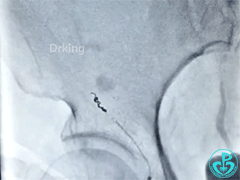

股动脉造影:

泥鳅导丝怎么用泥鳅导丝又惹祸,股动脉分支破裂要堵上!_https://www.jmylbn.com_新闻资讯_第3张

泥鳅导丝怎么用泥鳅导丝又惹祸,股动脉分支破裂要堵上!_https://www.jmylbn.com_新闻资讯_第4张

怎么办?

术者策略

我们用弹簧圈来封堵。一个不行就两个。终于堵住血管!